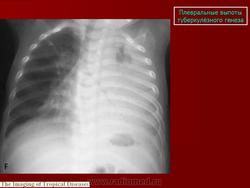

Туберкулёз. Плевральные выпоты туберкулёзного генеза. +

Плевральные выпоты туберкулёзного генеза.

1.vypot_.slayd11.jpg